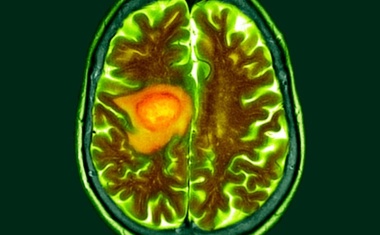

Glioblastome sind bösartige Gehirntumore mit bedrückender Prognose. Die mittlere Überlebenszeit der betroffenen Patienten beträgt bei einer optimalen Standard-Therapie zwölf bis 18 Monate.

Glioblastome sind besonders aggressive Hirntumore, die schnell auch in das gesunde Hirngewebe hineinwuchern. Da die Tumore chirurgisch meist nicht vollständig entfernt werden können, ist die Prognose von Glioblastom-Patiententen sehr schlecht.

Die Diagnose Glioblastom geht mit einer schlechten Überlebenschance einher. Der Gehirntumor zählt zu den aggressivsten Krebsarten.

Glioblastome sind bösartige Hirntumore mit schlechter Prognose, da sie in der Regel nicht auf gängige Krebstherapien ansprechen. Ein Grund hierfür ist, dass die Tumorzellen Mechanismen entwickelt haben, um sich der Immunabwehr zu entziehen.

Jedes Jahr erkranken in Deutschland rund 8.000 Menschen an einem Hirntumor. Als besonders aggressiv gilt dabei das Glioblastom, da die Tumorzellen schnell wachsen und in das gesunde Gehirn einwandern.